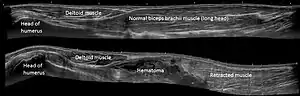

When a biceps tendon ruptures, the muscle belly changes position in the arm.[1] The bulge that forms is often known as Popeye's sign, due to the similarity in appearance to the cartoon character Popeye.[1]